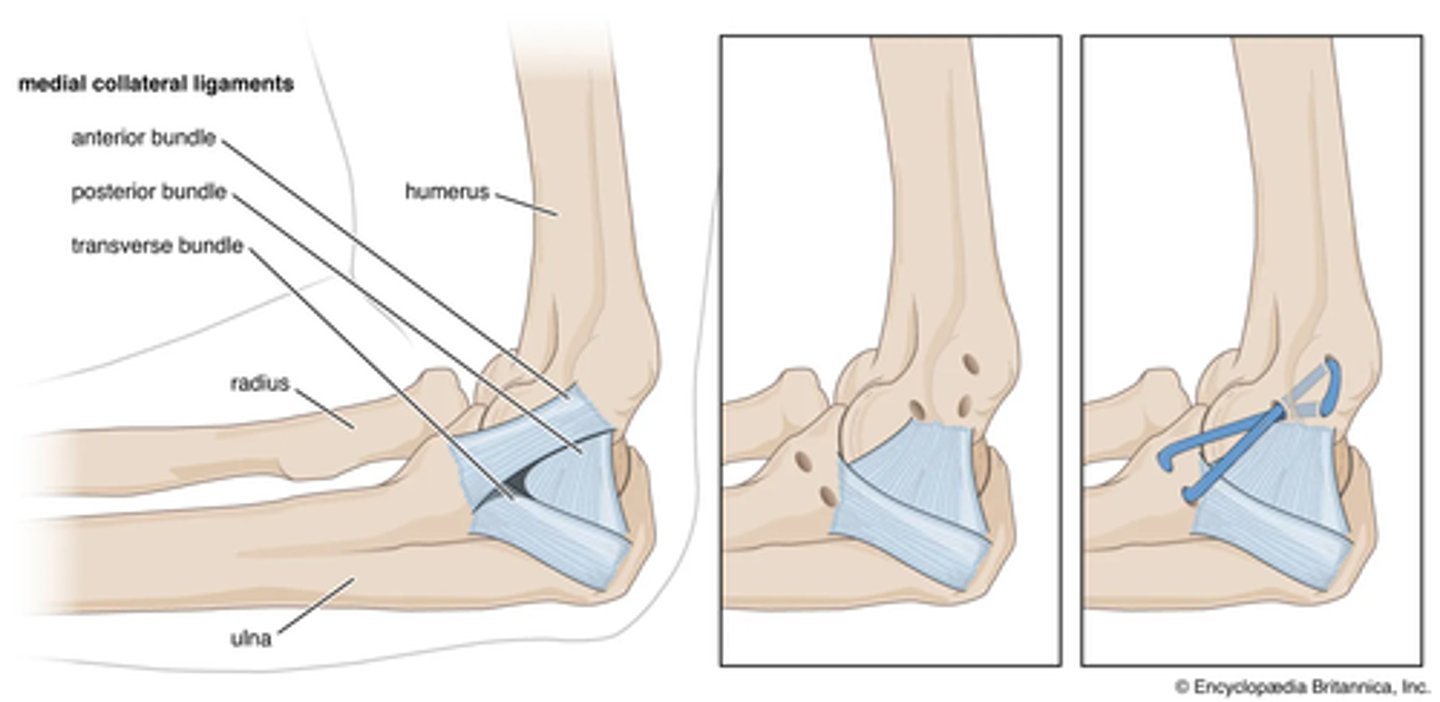

Radial collateral ligament

Anular ligament

Ulnar collateral damage